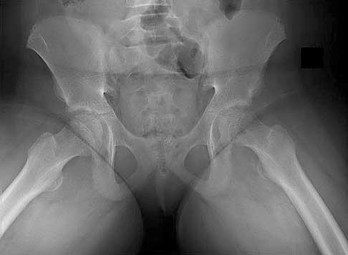

A 22-year-old male is brought to the trauma bay after a motorcycle accident. Pelvic radiographs demonstrate significant widening of the pubic symphysis, indicative of an anteroposterior compression (APC) injury. To classify this as an APC Type III injury (Young-Burgess classification), which of the following combinations of posterior pelvic ring ligaments must be completely disrupted?

Options:

Correct Answer: Anterior sacroiliac, posterior sacroiliac, sacrospinous, and sacrotuberous ligaments

Explanation:

In the Young-Burgess classification, APC I involves symphysis widening <2.5 cm with intact posterior ligaments. APC II involves symphysis widening >2.5 cm, disruption of the anterior sacroiliac, sacrospinous, and sacrotuberous ligaments, but the critical posterior sacroiliac (SI) ligaments remain intact (rotationally unstable, vertically stable). APC III indicates complete disruption of the anterior SI, sacrospinous, sacrotuberous, AND the posterior SI ligaments, resulting in a completely unstable hemipelvis (both rotationally and vertically).